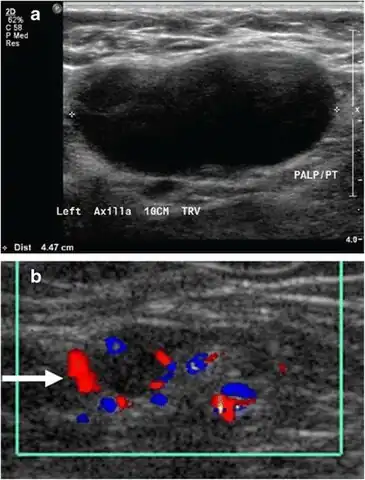

- Absence of the fatty hilum

- Increased focal cortical thickness greater than 3 cm

- Doppler ultrasonography that shows hyperaemic blood flow in the hilum and central cortex and/or abnormal (non-hilar cortical) blood flow.[25]

On ultrasound, B-mode imaging depicts lymph node morphology, whilst power Doppler can assess the vascular pattern.[27] B-mode imaging features that can distinguish metastasis and lymphoma include size, shape, calcification, loss of hilar architecture, as well as intranodal necrosis.[27] Soft tissue edema and nodal matting on B-mode imaging suggests tuberculous cervical lymphadenitis or previous radiation therapy.[27] Serial monitoring of nodal size and vascularity are useful in assessing treatment response.[27]